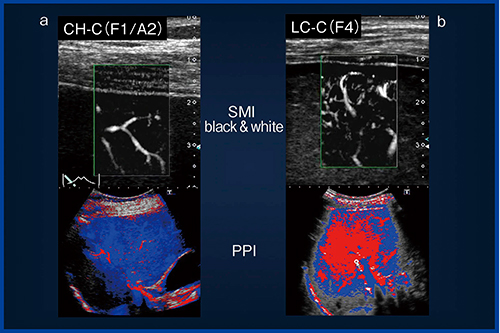

急性肝炎では,SMIで細かい血管が観察される急性期(図9a)には,造影超音波(PPI)では赤が広範囲に広がり動脈化が認められた。一方,SMIで動脈がほとんど観察されない回復期(図9b)には,造影超音波(PPI)も青が主体となり,門脈由来の灌流に回復していることが確認できた。

また,慢性肝炎と肝硬変を比べると,SMIで動脈が多く確認される肝硬変(図10b)では,造影超音波(PPI)でも動脈化が確認できるのに対し,動脈がほとんど見られない慢性肝炎(図10a)では,血流バランスが門脈に傾いていることがわかる。

図9 動脈が見える症例と見えない症例の比較:急性肝炎

図10 動脈が見える症例と見えない症例の比較:慢性肝炎と肝硬変